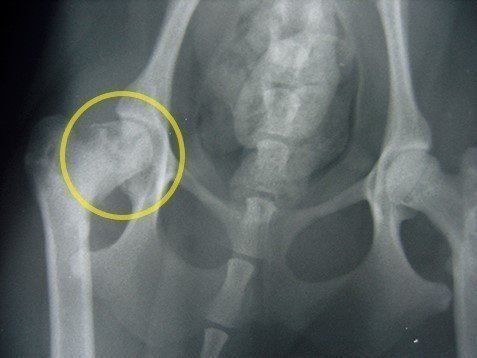

写真は、ゆるみが出ている関節のエックス線写真。向かって右側の関節にズレがみられる。

とくに子犬のうちは、見慣れない歩き方をしていても、クセや個性と勘違いしがち。子犬のうちに健康診断で動物病院に行き、エックス線写真を撮ってチェックしてもらうと早期発見につながります。